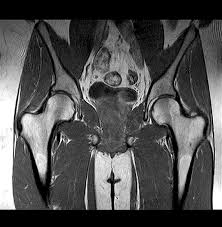

MRI Screening of Left HIP

Looking for a reliable centre for MRI screening of the left hip? Medifyhome is partnered with certified diagnostic centres to offer modern, affordable, and accurate left hip MRI screenings. This scan provides a clear view of the hip structure that helps diagnose conditions like hip fractures, arthritis, labral tears, and other joint problems. Using cutting-edge technology, Medifyhome ensures precise imaging that highlights soft tissues, muscles, ligaments, and cartilage around the hip. Our centres are NABL and NABH-accredited, ensuring premium quality and patient comfort. Medifyhome provides MRI left hip screenings in Chennai, Mumbai, and Hyderabad, making high-quality diagnostics accessible across major cities. For detailed pricing and assistance, reach out to us today. Book your MRI left hip screening online with Medifyhome for reliable and cost-effective imaging. Contact us at +919100907036 or +919100907622.

An MRI scan of the left hip is a safe test that uses magnets and radio signals to produce clear pictures of the bones, joints, and nearby tissues. This test is used for diagnosing hip pain, fractures, infections, arthritis, and other conditions caused by wear and tear. Unlike X-rays, MRI scans produce clear images without using radiation, which allows doctors to examine the soft tissues and joints closely. This test can reveal early signs of damage or disease, helping to start the right treatment.